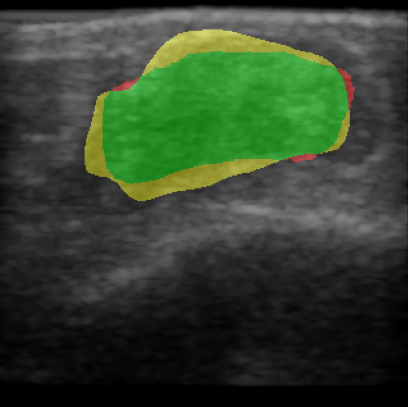

Chronic wounds including diabetic and arterial/venous insufficiency injuries have become a major burden for healthcare systems worldwide. Demographic changes suggest that wound care will play an even bigger role in the coming decades. Predicting and monitoring response to therapy in wound care is currently largely based on visual inspection with little information on the underlying tissue. Thus, there is an urgent unmet need for innovative approaches that facilitate personalized diagnostics and treatments at the point-of-care. It has been recently shown that ultrasound imaging can monitor response to therapy in wound care, but this work required onerous manual image annotations. In this study, we present initial results of a deep learning-based automatic segmentation of cross-sectional wound size in ultrasound images and identify requirements and challenges for future research on this application. Evaluation of the segmentation results underscores the potential of the proposed deep learning approach to complement non-invasive imaging with Dice scores of 0.34 (U-Net, FCN) and 0.27 (ResNet-U-Net) but also highlights the need for improving robustness further. We conclude that deep learning-supported analysis of non-invasive ultrasound images is a promising area of research to automatically extract cross-sectional wound size and depth information with potential value in monitoring response to therapy.